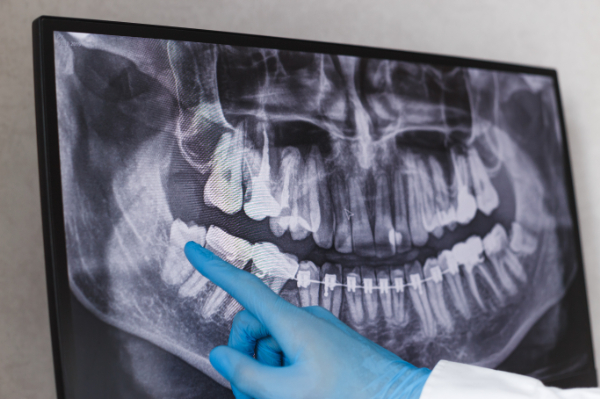

検査

抜歯前には、検査を行います。レントゲン撮影やCT撮影を行い、親知らずの生え方や神経・血管との位置関係を把握します。この検査によって親知らずを抜歯する難易度を判断し、当日の流れや麻酔方法を患者さまと共有することで、安心して処置を受けられる体制を整えます。